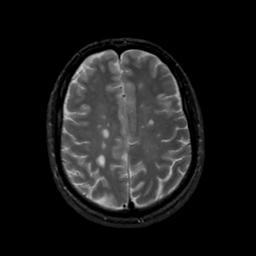

MR Study #16, June 23, 1991 -- Slice #36